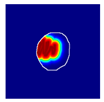

| True label: FSGS |  |  |  |  |  |

| single-multiclass: FSGS p = 0.964, IoU = 0.063 | |||||

| multiple-binary: FSGS p = 0.999, IoU = 0.076 | |||||

| spatially guided: FSGS p = 0.862, IoU = 0.390 | |||||